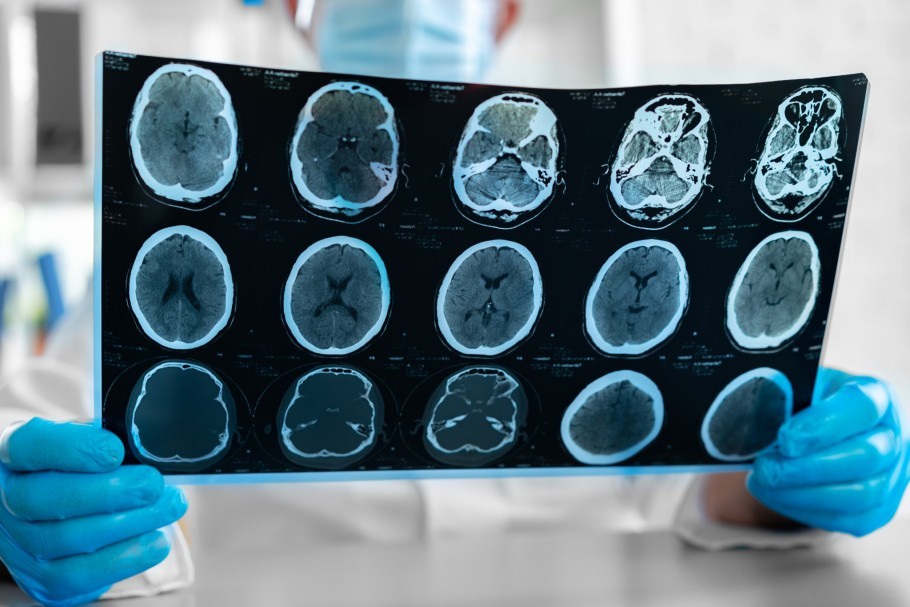

Endovaskuläre Therapieoptionen bei der Behandlung chronischer Subduralhämatome

Ltd. OÄ Dr. med. B. Ries

Institut für Radiologie und Neuroradiologie an der MUL